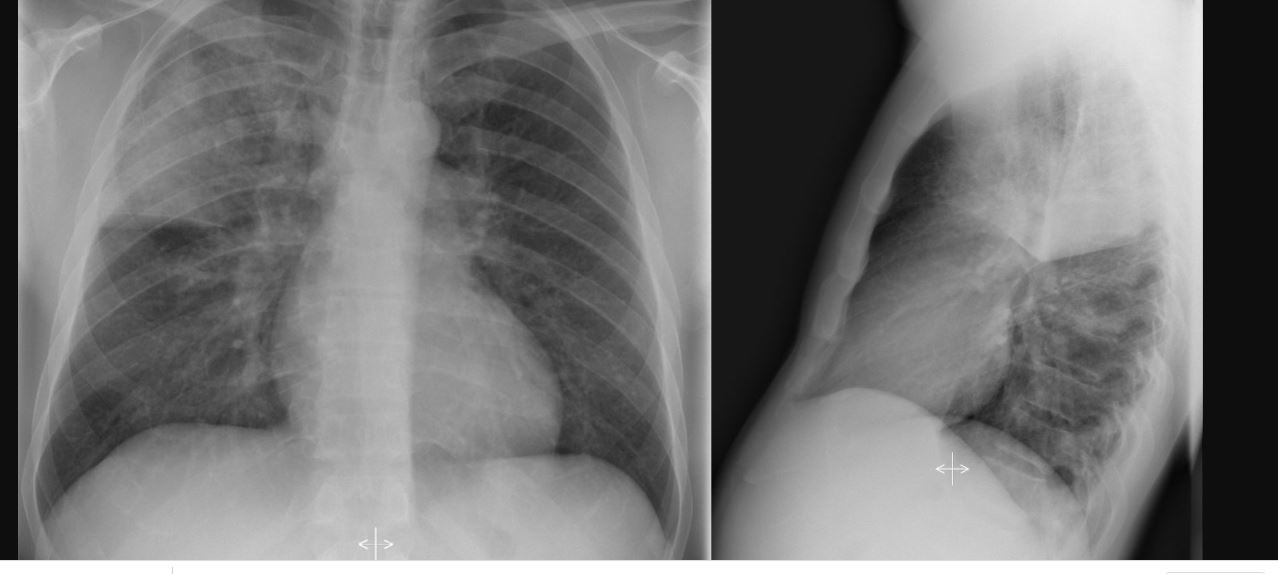

Dx?

A

Pneumonie lobe supérieur droit la pas plus compliqué que ca